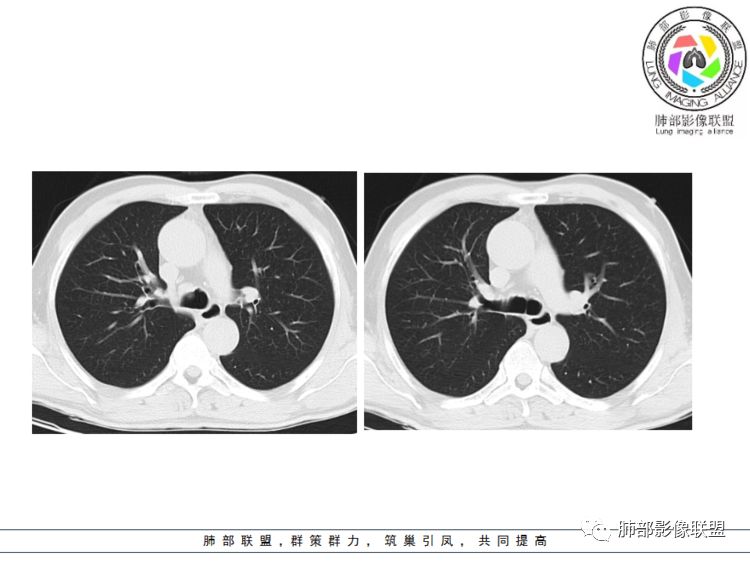

THINKER:隆突上气管右侧壁肿物,镜下表面不光滑,有苔,C下似有冰山征,考虑类癌

俞丽:气管腔右侧壁增厚呈丘状隆起并结节状向腔内突出,密度均匀,边缘光整,首先考虑乳头状瘤,腺样囊腺癌、鳞癌待排

常志强:老年男性,气管右侧壁肿物,宽基底,边界清晰,考虑恶性肿瘤,鳞癌可能,有增强就更好了

张帅:中年男性,体检发现,病变位于气管下1/3,以管腔内生长为主,向管壁、管腔外浸润。气管镜:气管下1/3可见新生物,表面呈结节状,可见少量白色坏死物。粘膜充血水肿不明显。病理怀疑病灶内有纤维组织,细胞成梭形(具体不会)。此区域以鳞癌及腺样囊性癌多见,结合病理基本可排除此诊断

傅昌瑜:55岁男性,右侧气管下段偏前侧后壁见软组织密度结节(无增强,但目测其密度与肌肉差不多,且镜下见为肿物),考虑为气管肿瘤;定性:结节基底部大于其最大横径(宽基底),结节与气管内壁的夹角呈钝角,无蒂,结节周围气管壁增厚僵硬,向纵隔侵犯,故考虑为恶性。气管内恶性肿瘤常见有鳞状细胞癌(最常见)、腺样囊性癌、粘液表皮样癌、类癌。年轻女性类癌相对多见,腺样囊性癌、粘液表皮样癌位置可能与腺体分布有关,多位于气管后方或侧后方。具体到这个病人考虑:气管鳞状细胞癌

Coke with ice:体检发现,软组织密度,边缘规整,病灶主体沿气管外缘走行,大部位于管腔外,局部向腔内突入,邻近气管软骨未见明显破坏,考虑良性病变

生来征服-浪子:患者中年,无任何临床症状,气管右侧壁软组织密度影,宽基底位于气管壁,向腔内腔外生长,形态规则,首先考虑良性或者低度恶性肿瘤。无任何阻塞性表现,不考虑鳞癌

病灶跨气管壁内外,主体在外;边界清,密度均匀

明显看到气管壁软骨受压内移

局部是撑开的,就是说软骨不是破坏

表面隆起,有小斑点

无症状;倾向于良性,平滑肌瘤?神经源性肿瘤?不除外其他

病例小结      气管神经鞘瘤属于罕见的气管良性肿瘤,一般气管良性肿瘤或腔内或腔外生长的结节样改变,恶性肿瘤呈腔内外生长,但本例肿块向腔外生长,呈“冰山样改变”,即肿瘤的腔内部分较小而腔外部分较大,无周围组织侵犯。因此肿瘤腔内外生成不能作为鉴别气管良恶性肿块的绝对依据。        因此冠(矢)状位多平面观察、软骨是否破坏、气管壁有无增厚等细节观察,对于鉴别气管肿块良恶性有重要的参考性。